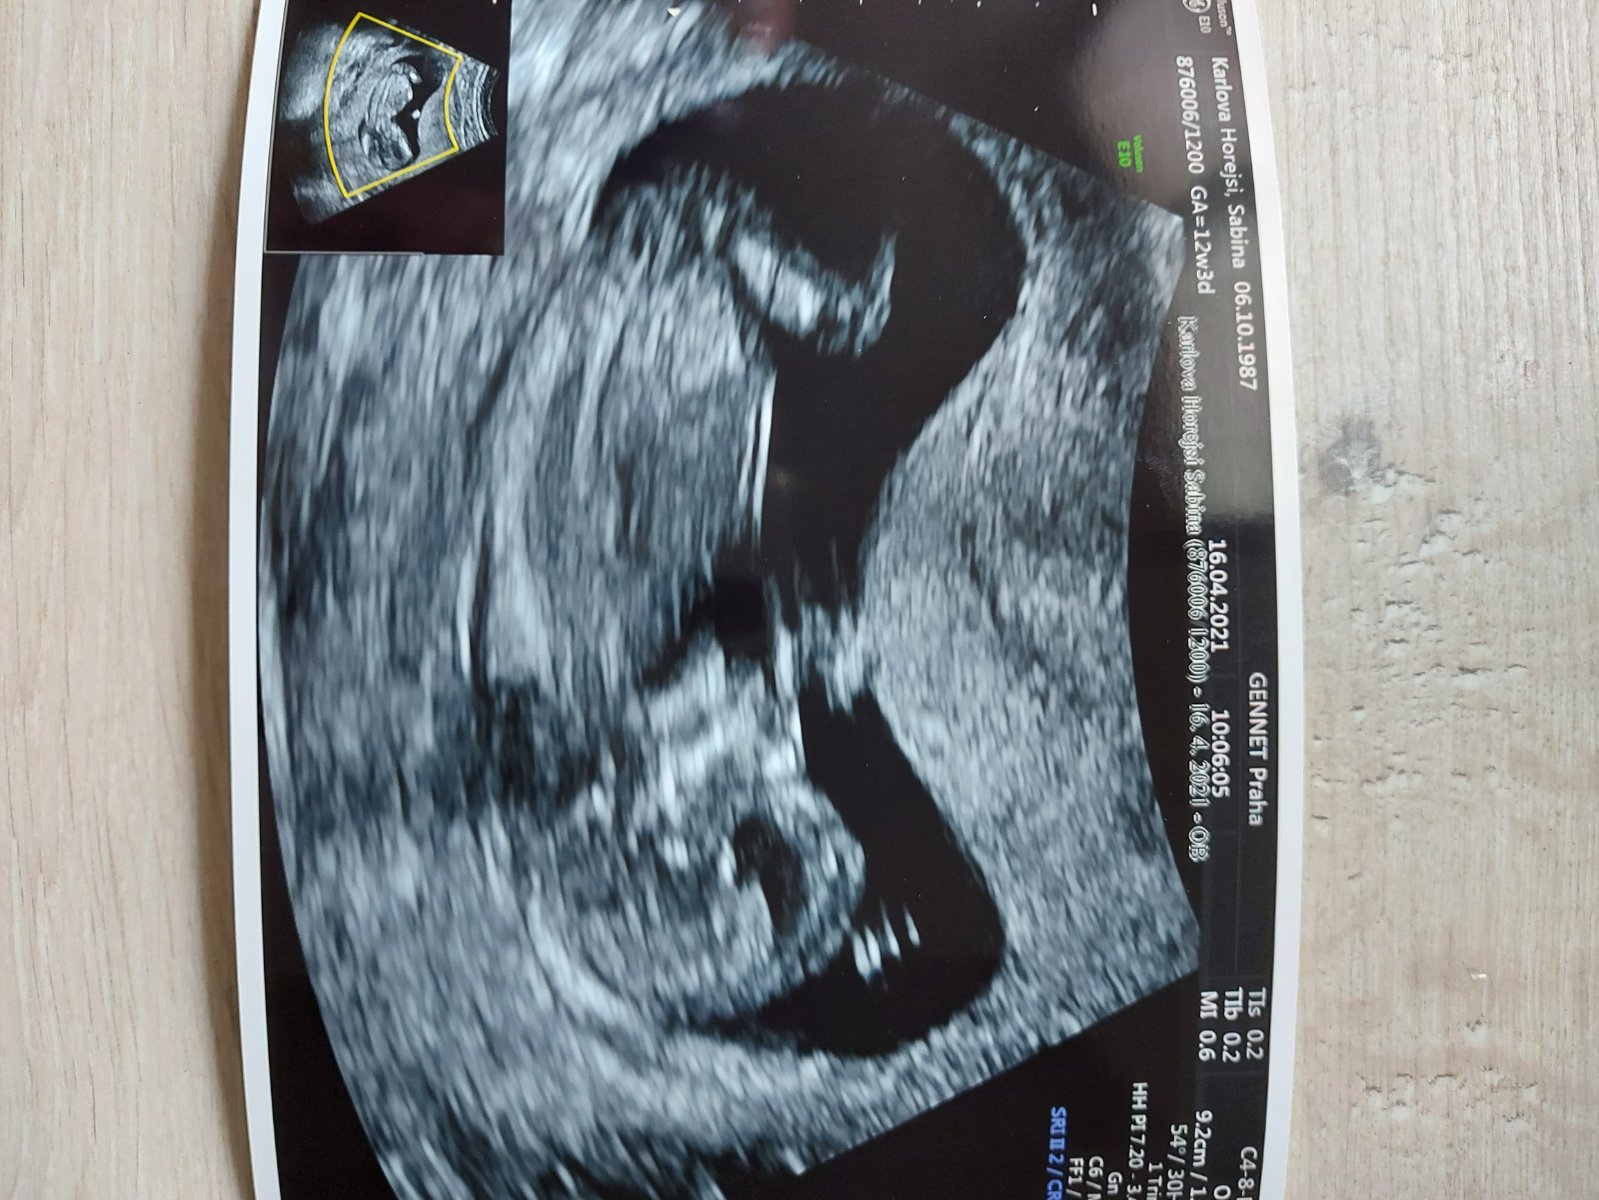

Ahoj holky, sem stará a nedočkava 🙂 nenajde se některá, která má pohlavi z utz zmakle a nenapovi mi? Dekuji

na odpověď mas blbou fotku. Teda pěknou, ale z tyhle se to nepozna

@jijulka ja myslela podle hrbolku nebo co 🙂🙂

Tady s toho úhlu opravdu zadny hrbolek nejde vidět , to musí být hrbolek přímo mezi nožičkami , a mě doktor řekl že hrbolek směřuje náhodu 70% kluk ted 29 TT a je to kluk , u holek mi řekli že nejde nic vidět a pohlavo holčiček mi potvrdili až 22tt

@sabinakarlova Podle hrbolku sice ano, ale to by musel byt na te fotce videt.

Tady není hrbolek vidět, takže se to nedá poznat.

My to třeba poznali už tady. Jasně, nebylo to ještě 100%ní, ale holčičku jsme trefili